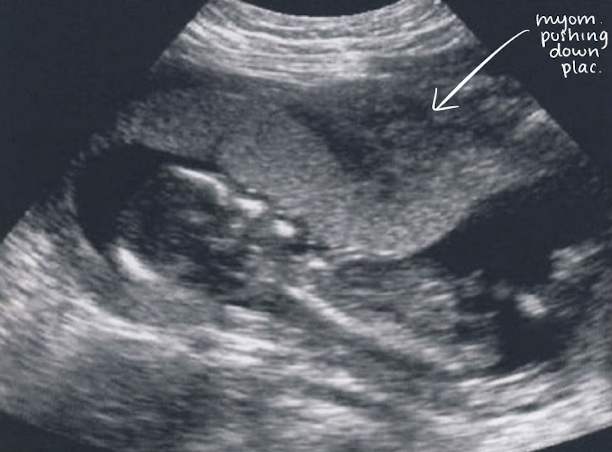

3 ways placenta appearance can be temporarily altered

placental migration

distended bladder

Braxton-Hicks contraction

refers to when placenta changes position in uterine cavity

primarily explained by 2 theories:

LUS growth theory (when expanding uterus pulls placenta upward)

trophotropism theory (atrophic placenta in areas of low blood supply)